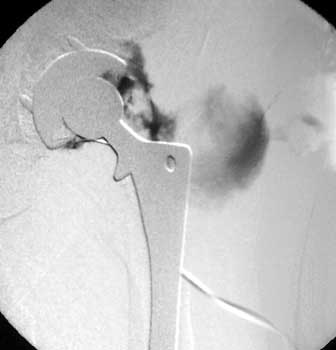

Dry tap secondary to large greater trochanteric bursa, 20

gauge spinal needle placed in bursa under fluoroscopic guidance

Scar with focal area of drainage. Dry tap secondary to large greater trochanteric bursa with

sinus tract draining to skin

Sinus tract draining posteriorly